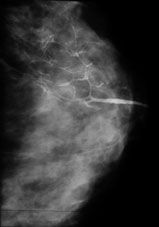

La galactographie montre une dilatation du canal, une image correspondant à 1 ou plusieurs papillome, un rétrécissement ou une amputation de la lumière. Parfois le liquide entoure une calcification.

Les résultats de cet examen permettent d'identifier une tumeur bénigne (85% des cas) et beaucoup plus rarement un cancer.

Les images ne permettent pas de poser un diagnostic et l'exérèse de la lésion est nécessaire.

Galactographie normale Papillome Galactocèle